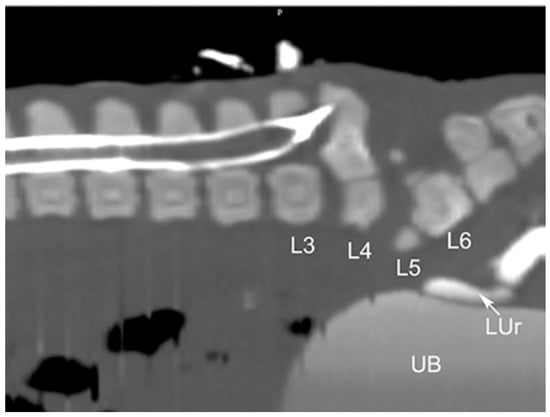

| 1 * | None | partial aplasia of L4, quite complete aplasia of the vertebral canal of L5, partial aplasia with absence of the vertebral canal of L6; scoliotic deviation toward the right. | partial aplasia of S1 with absence of the vertebral canal. | Coccygeal vertebrae: no visible abnormalities other abnormalities: duplication of the first tract of the ureters; caudal dislocation of the left kidney with a dorso-medial bended shape and some cortical small cists |

| 2 * | None | the lumbar tract showed a lordotic and scoliotic curvature; L2-L3-L4 were irregularly fused and L3-L4 without a vertebral canal; L5 and L6 were present only as a bud of the body with the agenesia of the vertebral arch. | S1 and S2 missed the vertebral canal and were irregularly articulated | Coccygeal vertebrae: only the first five metameric were visible |

| 3 * | None | the lumbo-sacral junction showed a slight lordotic curvature; L6 missed the vertebral canal. | S1 was present only as a bud of the body with the agenesia of the vertebral arch | Coccygeal vertebrae: Only four coccygeal vertebrae were present. |

| 4 ** | T14 was partially fused with L1. | L1 was partially fused with T14 and its body was wedge shaped (hemi vertebra) L2 had a dysplastic vertebral canal and was partially fused with L3; the residual lumbar vertebrae were present only as a bud, without a vertebral canal and with a scoliotic curvature toward the left | S1 was present as a small bud, the remnant were partially fused and with a kyphotic curvature. | Coccygeal vertebrae: Visible until the Co15 with some hemi vertebrae. Other abnormalities: Partial fusion of the left 13th and 14th ribs; the pelvis was tilted toward the left; severe hyper extension of the left knee with inversion of the normal angle. |

| 5 ** | Visible T16 with a complete aplasia of the vertebral canal. | vertebrae L1 had only a slight mineralization of the body and the remnant (L2-L6) were present only as a bud of the body with a complex lordotic-scoliotic curvature toward the right. | the body of S1 was partially fragmented and without the vertebral canal; S2 was visible only as a small bud; no other sacral vertebrae were visible. | Coccygeal vertebrae: The coccygeal vertebrae were absent. Other abnormalities: both the knees had an inverted angle. |

| 6 ** | Visible T15 | partial aplasia of L2 with an incomplete vertebral canal; L3 without the vertebral canal and a right fragmented lateral process; the remnant lumbar vertebrae (L4-L6) were present only as a bud of the bodies and with a lordotic curvature. | partial dysplasia of the body of S1 with a not fused cranio-ventral portion of the body and without the vertebral canal. | Coccygeal vertebrae no visible abnormalities. |

| 7 ** | None | partial aplasia of L4 without the vertebral canal; L5 and L6 were present only as a small bud of the bodies. | no visible abnormalities | Coccygeal vertebrae no visible abnormalities Other abnormalities Severe hyper extension of both the knees and the tarsi. |

| 8 ** | None | L1 was dysplastic with bifid dorsal process and the vertebral canal communicating with the dorsal soft tissues of the lumbar tract; absence of the vertebrae from L2 to L4; L5 and L6 partially fused and with aplasia of the vertebral canal. | Sacral vertebrae S1 and S2 were partially fused and irregularly fragmented without the vertebral canal. | Coccygeal vertebrae no visible abnormalities. |